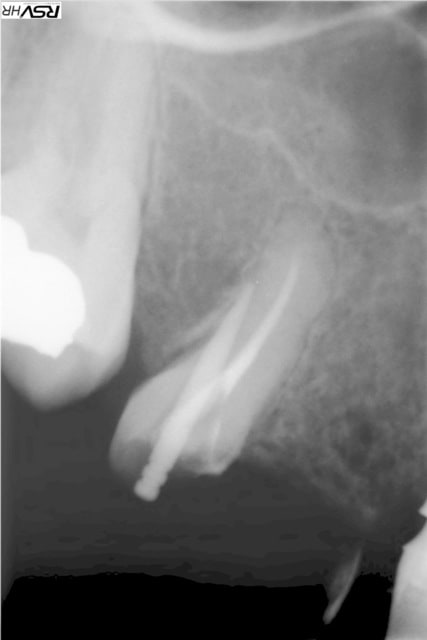

1° CAS une belle perf traitée avec du Biodentine. Résultat à 2 ans.

2°CAS expulsion - réimplantation immédiate - à 3 ans résorption interne - biodentine . le résultat est sans commentaire.

voilà les photos

1 hlkygf - Eugenol

2 jvxkl9 - Eugenol

3 owbzxu - Eugenol

6 alrbjd - Eugenol

3 iwmo8e - Eugenol

sorry je m'étais planté sur la dernière photo.

Heureusement que personne n'a réagit et crié à l'escroquerie !

4 a2icey - Eugenol